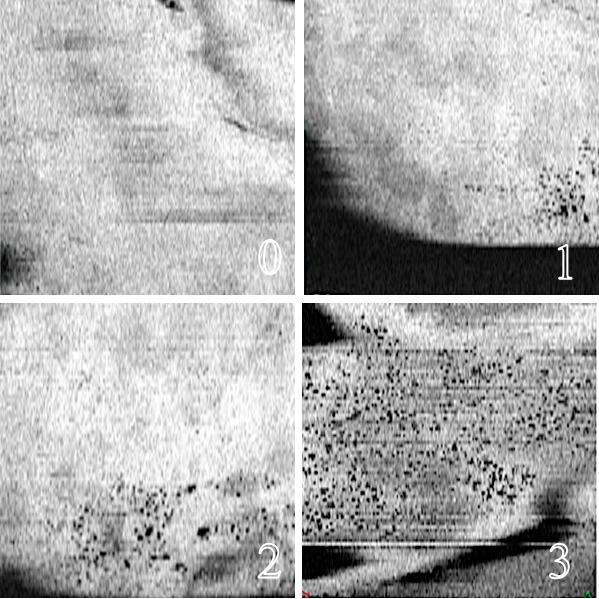

We evaluated 20 blebs of 20 patients after a first-time trabeculectomy. Conjunctival vascularization was quantified using ImageJ software. Eyes were classified into two groups according to the preoperative conjunctival vessel density: hypovascularized conjunctiva (HypoV; 10 eyes) and hypervascularized conjunctiva (HyperV; 10 eyes). The density of intraepithelial microcysts (0 to 3) was also analyzed.

There were significantly more needling procedures in the HyperV group, with 70% of the eyes undergoing needling during follow-up compared to 20% in the HypoV group ( = 0.012). In the HyperV group, 50% of the eyes required IOP-lowering eyedrops after surgery, compared to 10% in the HypoV group ( = 0.029). HypoV showed significantly more intraepithelial microcysts than did HyperV at 1 week (1.1 vs. 0.4, = 0.0215), 1 month (2.2 vs. 0.4, = 0.0003), and 6 months postoperatively (2.0 vs. 0.7, = 0.0068). A statistically significant correlation was found between preoperative conjunctival vascular density and mean IOP at 1 week ( = 0.483, = 0.038), 1 month ( = 0.714, = 0.001), and 6 months postoperatively ( = 0.471, = 0.043). There was no statistically significant correlation between the preoperative conjunctival vascularization density and the eyedrop-year rate ( = 0.036, = 0.8704) or the preservative-year rate ( = 0.1444, = 0.5107).

Poor conjunctival vascularization was associated with lower IOP and a higher number of intraepithelial microcysts evaluated with OCT-A. OCT-A provides a simple, noninvasive, and reproducible method to analyze and quantify bleb vessels before and after filtering surgery.